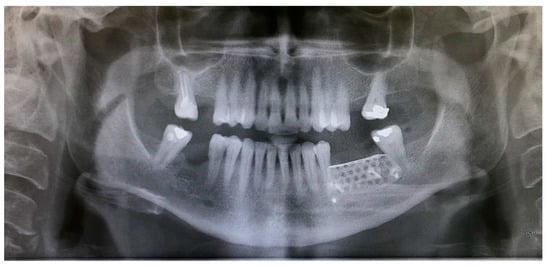

- The sutures were removed on day 21. A panoramic radiograph was taken after surgery. (Figure 8). Periodic controls were scheduled; every week during the first 2 months, every two weeks in the third and fourth months, and once a month up to 6 months.